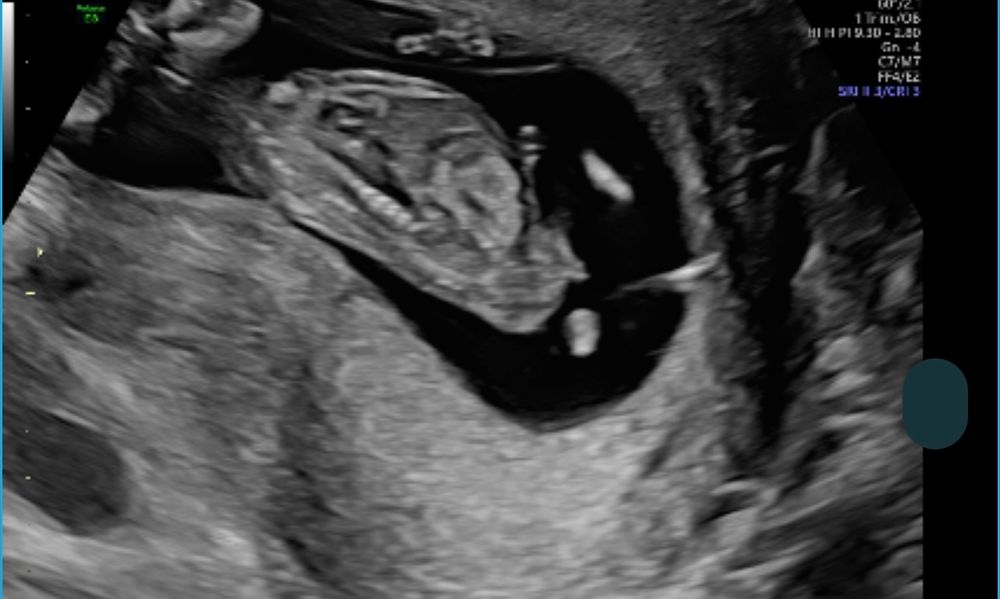

и по узи я вижу , что девочка ?

Вполне возможно, что и правда девочка, вроде этот бугорок между ножек у девочек параллельно телу, а у мальчиков чуть вздёрнут. Я делала в 12 недель 3д узи, там было очень хорошо видно вздернутый бугорок, врач сказала, скорее всего мальчик, мы кровь ещё сдавали и пол подтвердился.